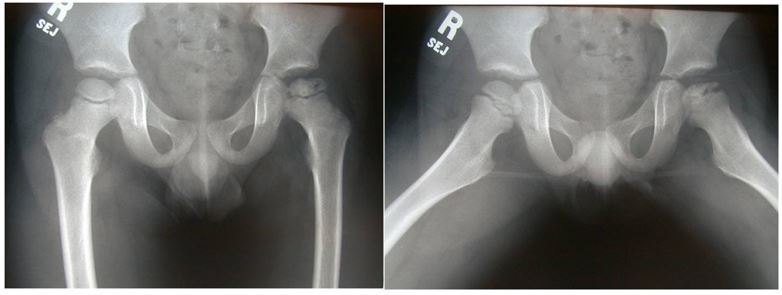

1.Describe this plain radiograph.

Pelvic radiograph of a skeletally immature child with dislocated left hip due to DDH as evidenced by

- dysruption of Shenton’s line

- femoral head is NOT below the Hilgeriner line and NOT medial to the Perkin’s line

- small femoral head ossific nucleus

- shall acetabulum as acetabulum index is > 25

1. How may a child with such pelvic radiograph present clinically?

Late presentation after child starts to weight bear

- LLD with affected side (left side) demonstrating short limb gait with toe walking, bending of knee at the longer limb,higher knee level, Trendelenburg gait, lurching towards affected side, externally rotated lower limb.

- Examination: shortening at femoral component, limited ABDuction, excessive IR and ER

2. If both hips are involved, how will his presentation differ?

Waddling gait with side to side lurching

Excessive lumbar lordosis